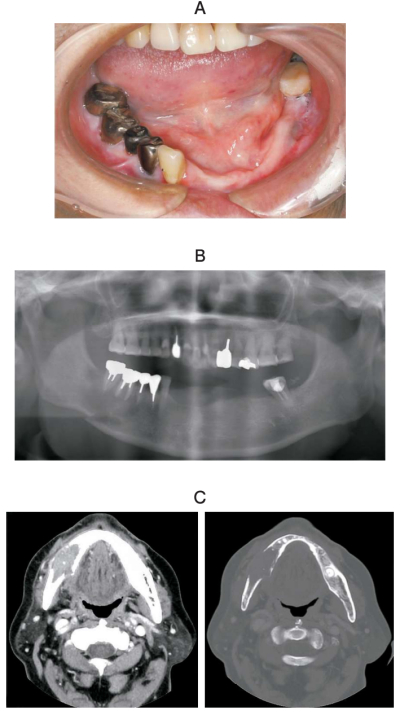

82 歳の女性。下顎右側臼歯部の咬合痛を主訴として来院した。5日前に気付いたがそのままにしていたという。下顎右側臼歯部歯肉に異常はないが、右側のオトガイ神経支配領域に感覚異常を認める。初診時の口腔内写真、エックス線画像、造影 CT及び生検時の H-E 染色病理組織像を別に示す。

診断名はどれか。1つ選べ。

b. 扁平上皮癌